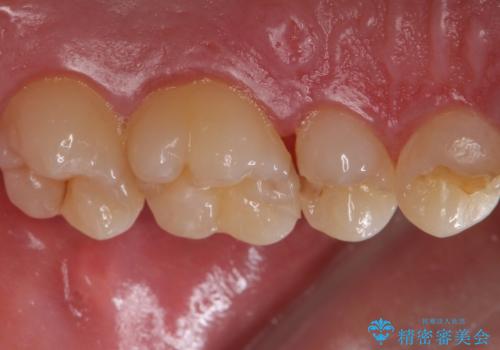

歯と歯の間の虫歯 セラミックインレーでの治療

- 検査の結果虫歯が見つかった患者様です。

レントゲン画像と視診から詰め物で対応可能と判断したためインレーでの修復をしていきます。

- 左上5 セラミックインレー/77,000円費用は治療当時の料金となります

適合の良いインレーは段差がない上にセラミックは汚れがつきにくい材料であるため今後の虫歯発生リスクを抑えることに繋がります。